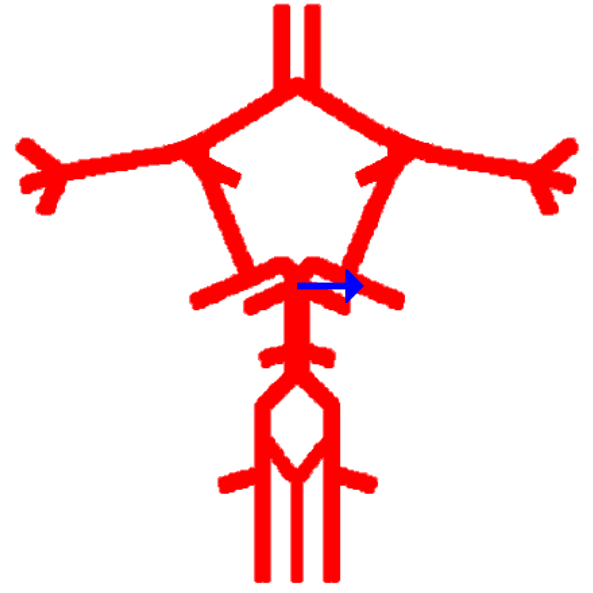

Label this cerebral artery

Basilar artery

Label this cerebral artery

Anterior communicating artery